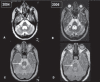

MR imaging in multiple system atrophy: its role in "splitting" parkinsonism